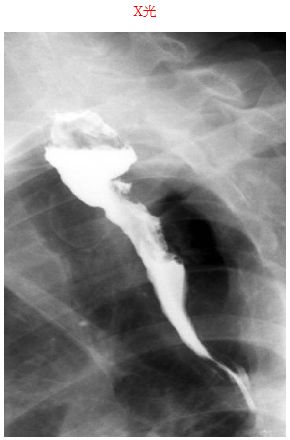

17. 一位54歲男性國中老師,一般健康狀況良好。近日中,吞時候會感到胸痛,但沒有體重減輕現象。其胸部X光及心電圖均正常。安排上消化道檢查,結果如附圖,下列何者正確? (A) 這是食道癌,應安排胸部CT Scan (B) 這是食道憩室,病人可有食物反芻現象 (C) 這是食道運動性障礙可以安排24小時PH監測 (D) 這是瀰漫性食道收縮(diffuse esophageal spasm),與其生活壓力有關 (E) 這是逆流性食道炎的一種表現,可先以質子幫浦抑制劑(PPI)治療。